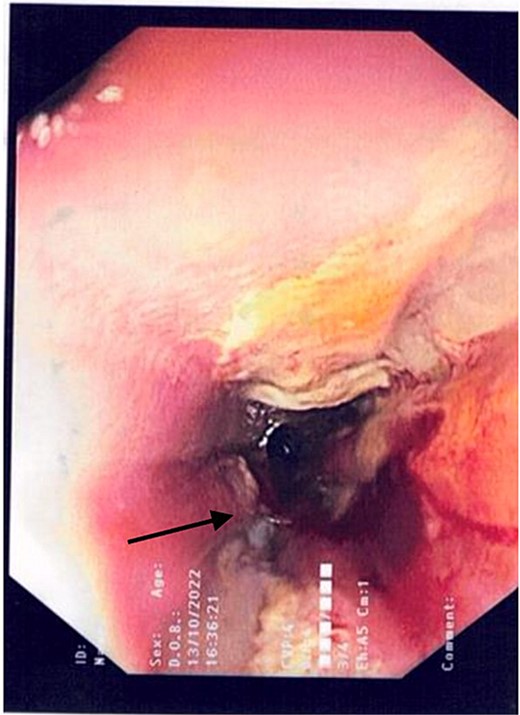

2L of pus was evacuated during laparoscopy, and it was converted to open due to limited views. At this stage, there was no obvious perforation. The entire colon was inspected, following splenic flexure and caecal mobilization. On inspection of the stomach, the wrap was intact with an unremarkable leak test. The decision was made to proceed with gastroscopy, whereby a 3 mm pinhole defect was seen at the GOJ at the 9 o’clock position, as shown in Fig. 2. Three haemostatic Cook Medical Instinct clips were placed, from distal to proximal, ensuring there was stable apposition of the perforated mucosa prior to deploying, as demonstrated in Fig. 3. Following this, the NGT was re-inserted under vision. The midline laparotomy was partially closed and Abthera dressing placed. The patient was taken to ICU intubated, with definitive closure performed 48 h later.

Gastroscopic image demonstrating the pinhole defect of the GOJ at the 9 o’clock position (arrow).